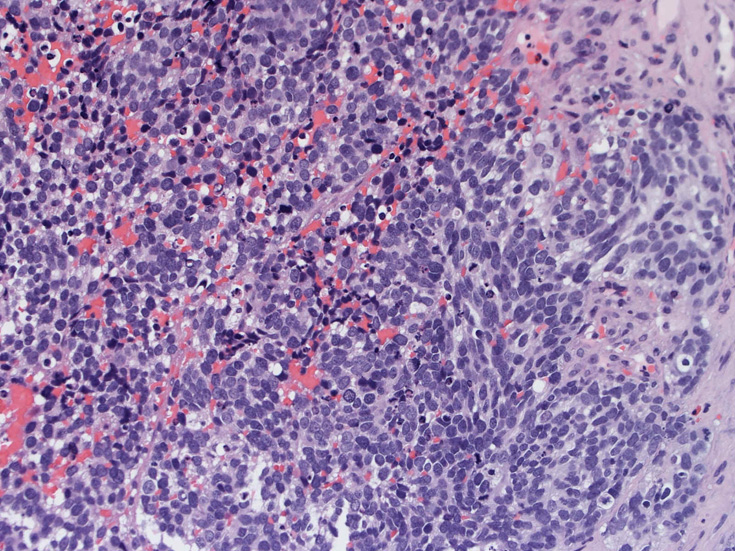

症例--鼻腔腫瘤

30歳代男性 鼻腔腫瘤の生検組織

厳密にはalveolar patternが明らかではなく, solid typeに入る症例かもしれない。異型細胞増殖胞巣が線維化組織に取り囲まれるように散在している. 小さな生検組織のため全体像が不明である。

鼻腔腫瘤生検組織